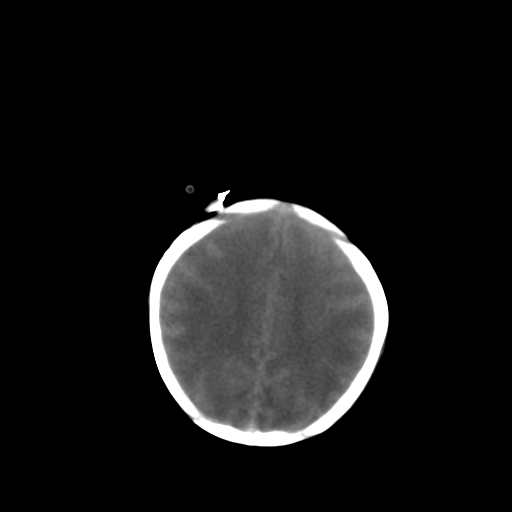

男,2天,孕31周早产儿,出生后窒息3分钟,精神反应差。

脑实质弥漫低密度,灰白质界限不清:结合临床考虑重度hie

孕31周的表现跟这差不多,但临床有窒息史,有症状,支持考虑hie